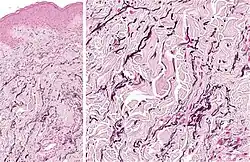

According to histopathology, there may be more localized wavy fibers in the dermis, which are visible when elastic staining separates normal from hypertrophic collagen bundles.[3] There may be fragmentation or aggregation of the elastic fibers in the deep and upper dermis.[2] Fragmented elastic tissue, microfibrillar or granular constituents, and aggregated elastin are visible under an electron microscope.[4]

Histopathology: Accumulation of fragmented elastotic material within the papillary dermis and transcutaneous elimination of elastotic fibers.[5]